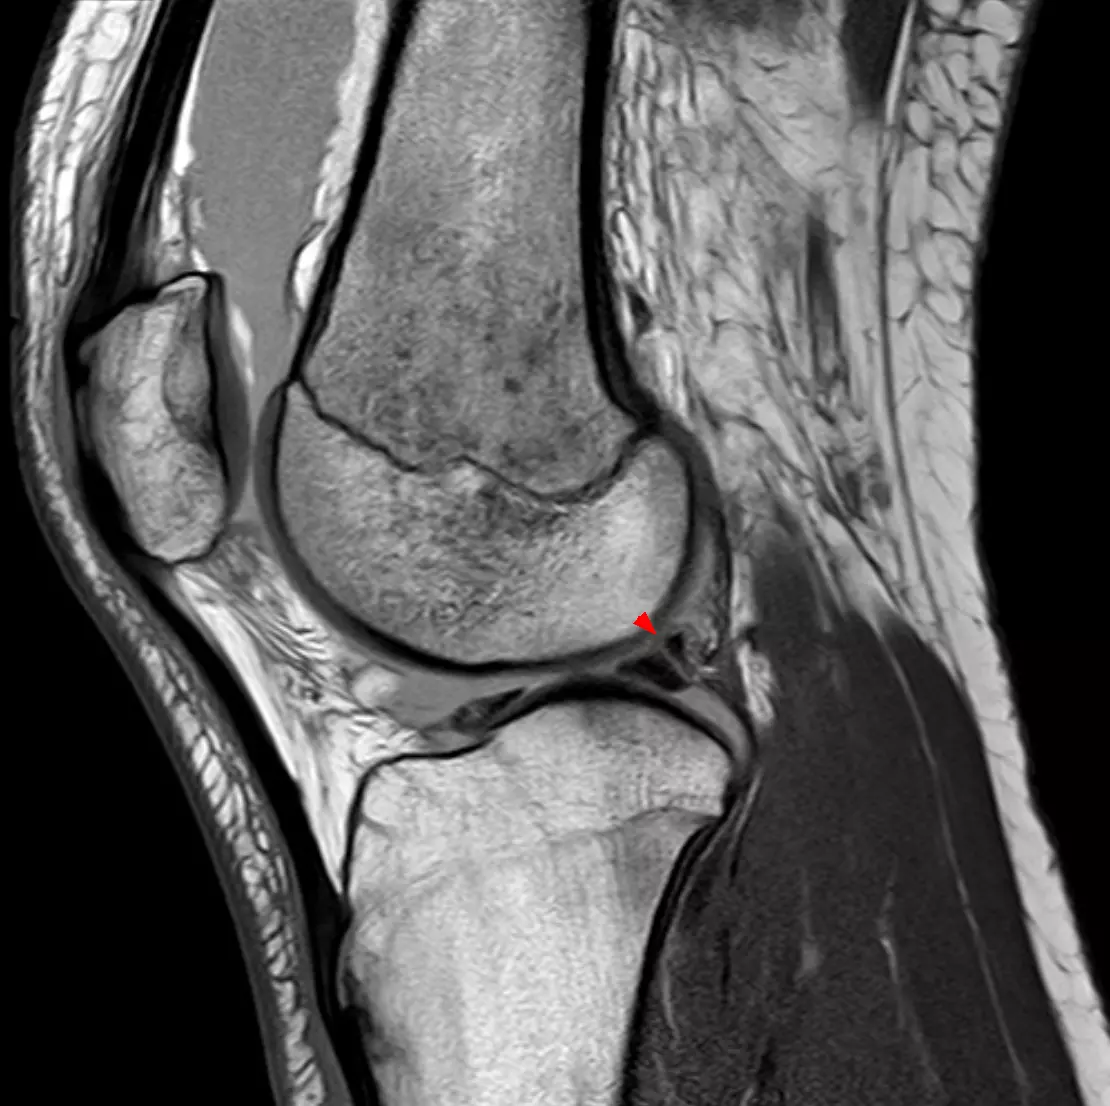

Vršimo operativno lečenje meniskusa i ligamenata kolena u Novom Sadu.

Naša ortopedija važi za najbolju ortopedsku polikliniku u celom Novom Sadu. Bavimo se operativnim lečenjem meniskusa i ligamenata kolena.

Brzo, nepovratno i, pre svega, bezbolno, operativnim putem otklanjamo sve probleme meniskusa i ligamenata koji Vas muče i tretiramo sve smetnje. Zahvaljujući ovakvom načinu lečenja stekli smo reputaciju najbolje ortopedske poliklinike u Novom Sadu.